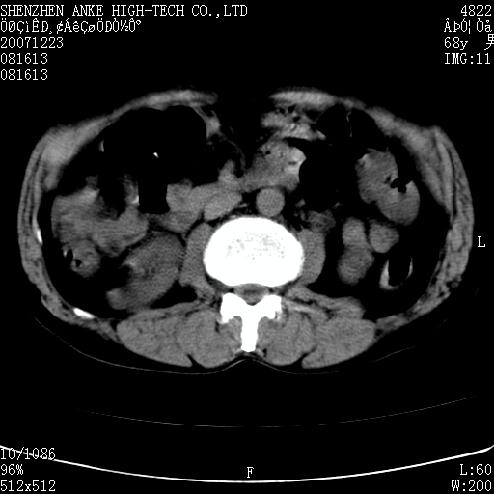

患者:男,63岁,2年前胆囊切除术后,现右上腹部剧烈疼痛近2天.

肠管积气明显.

肠道准备不好,干扰影大。

肠道气体伪影干扰太大了,应该是干扰所致,未见明显异常。

上腹部ct平扫未见明显异常。(肠道气体较多,患者呼吸了)

检查前最好叫病人喝些泛影葡胺,胃肠准备一下比较好